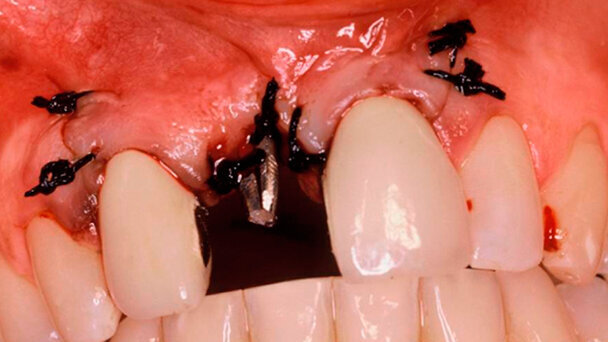

Il caso (Figg. 2-25) si riferisce a una giovane paziente di razza caucasica di anni 24 (anno 2000) arrivata alla nostra attenzione con un ponte da 2.1 a 2.3. La paziente riferì che la soluzione del ponte le era stata proposta dopo il tentativo di innesto di tessuto osseo eterologo per la collocazione, in seguito, di un impianto osteointegrabile bifasico. Il fallimento dell’innesto ha comportato una notevole perdita dello spessore del tessuto osseo impossibilitando l’inserimento dell’impianto. La correzione dell’edentulia caratterizzata da marcata atrofia ossea è stata effettuata utilizzando la metodica sopra descritta e finalizzata protesicamente con una corona definitiva in oro-ceramica. Il caso è stato seguito clinicamente per 16 anni (2000-2016).

Nel caso presentato si è usato un impianto MUM titanio grado 4 (certificato UNI CEI EN ISO 13485.2012) (Cami-Pedrazzini Srl, Milano, Italia), diametro 2,1-2,6 mm alla spira. Un ago tipo Scialom si usa come struttura di supporto per il bilanciamento profondo. L’elemento possiede un diametro di 1,2 mm e la lunghezza è variabile in modo che si possa ottenere sempre il bicorticalismo. Gli impianti ad ago vengono realizzati in titanio grado 4 e certificati per uso medicale (certificato ASTM F67 ISO 5832-2) (Acerboni implantologia, Casargo LC, Italia). L’inserimento dell’ago avviene in direzione divergente rispetto all’impianto principale; pur sempre mantenendo l’integrità dei denti contigui, esso deve essere spinto in profondità fino al raggiungimento della corticale profonda. In seguito, una volta raggiunta la profondità di impatto viene saldato tramite la saldatrice endorale di Mondani. La fusione avviene in corrispondenza dell’emergenza osteomucosa per formare un unico moncone protesico. La biocompatibilità della saldatura che avviene in bocca sulle parti sporgenti degli impianti è dovuta al tempo estremamente ridotto in cui passa la corrente tra anodo e catodo (2 mms), oltre alle caratteristiche intrinseche del titanio (cattivo conduttore di corrente) che la rendono totalmente sicura anche in presenza di sangue, saliva e acqua14-16.

Per preparare il sito dell’impianto monofasico, dopo l’apertura del lembo, vengono utilizzate le frese autocentranti di Pasqualini, con diametro progressivamente crescente fino a 2,5 mm17,18. Queste vengono montate su micromotore con raffreddamento liquido (soluzione fisiologica). Si comincia con una fresa sonda del diametro di 1,1 mm con la quale si raggiunge la corticale profonda. In seguito si realizza un controllo radiografico e si riporta la misura ottenuta sulle frese autocentranti terminando così la preparazione del sito implantare. La punta delle frese autocentranti è di forma triangolare tagliente mentre il dorso mantiene la forma triangolare ma risulta smussato. Questa forma particolare permette la creazione di tunnel osteotomici atraumatici e particolarmente precisi19,20.

L’inserimento dell’ago sfrutta la stessa preparazione iniziale con la fresa sonda da 1,1 mm per il raggiungimento della corticale profonda. Nel foro osseo così ottenuto si inserisce l’ago di 1,2 mm e lo si accompagna lungo il tragitto preparato con tecnica press-fit mediante un martelletto chirurgico.